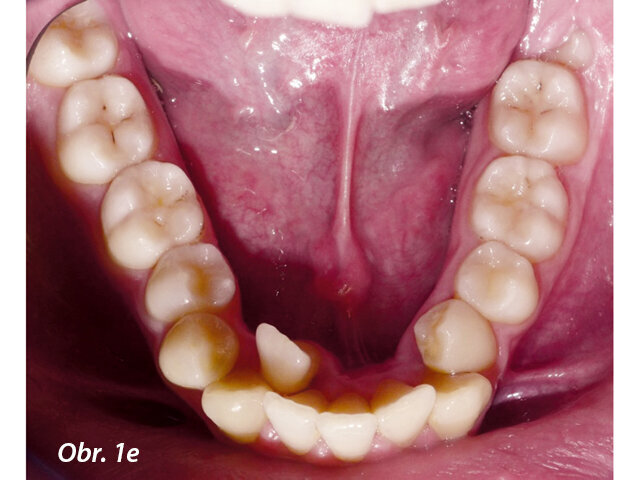

17letý chlapec přišel na konzultaci v prosinci 2014. Při intraorálním vyšetření bylo zjištěno: vztah molárů v I. třídě dle Anglea oboustranně a vztah špičáků v I. třídě vlevo a II. třídě vpravo. Šířka horního zubního oblouku v úrovni molárů byla normální, v místě premolárů však byl zubní oblouk výrazně zúžený a v mezišpičákové oblasti bylo výrazné stěsnání. V dolním zubním oblouku (úzký, tvar paraboly) bylo stěsnání s úplným deficitem místa pro zub 42, který byl v ektopické lingvální poloze. Hloubka skusu byla stoprocentní s traumatickým nákusem do gingivy v okolí dolních frontálních zubů. Zuby horního oblouku byly mírně větší než průměr, s malým nepoměrem Boltonova indexu. Objektivní extraorální vyšetření odhalilo syndrom dlouhého obličeje, vývoj střední třetiny obličeje byl normální a nazální pyramida byla široká ve spojení s mírnou mandibulární retruzí (obr. 1a–h).